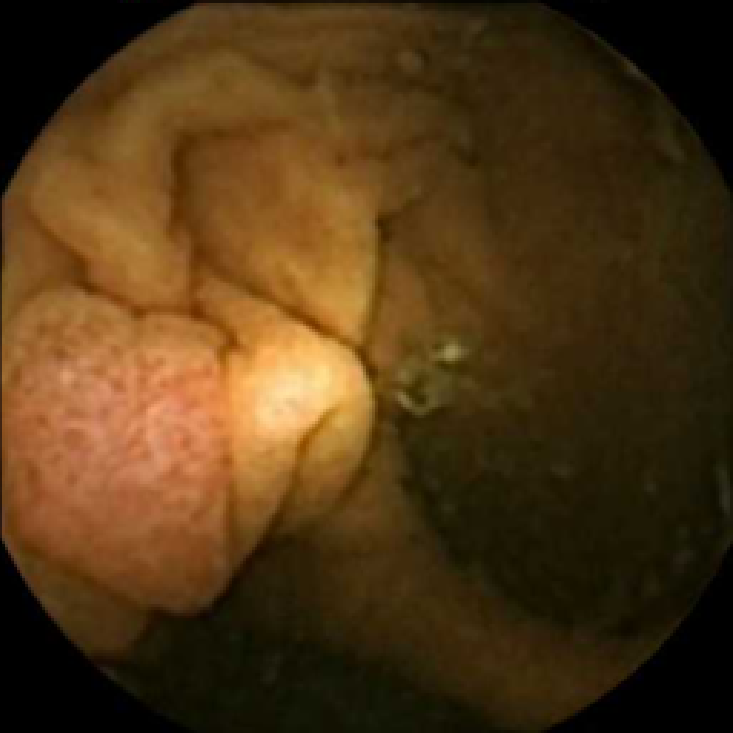

We illustrate the above considerations in Figure 4, where we compare the ellipses of inertia for a polyp frame and two frames with pronounced mucosal folds. The ellipses we plot are

| (20) |

where . The scaling term in front of is chosen so that the area of the ellipse of inertia is the same as the size of the corresponding feature.

As expected, we observe that the ellipses corresponding to mucosal folds (feature 2 in the second row and features 2 and 3 in the third row of Figure 4) are indeed much more stretched out than the ellipse corresponding to a polyp (feature 1 in the first row of Figure 4). Stretched ellipses imply higher eccentricity, thus we impose the following criterion

| (21) |

with some threshold to select moderately stretched features that are more likely to correspond to polyps.